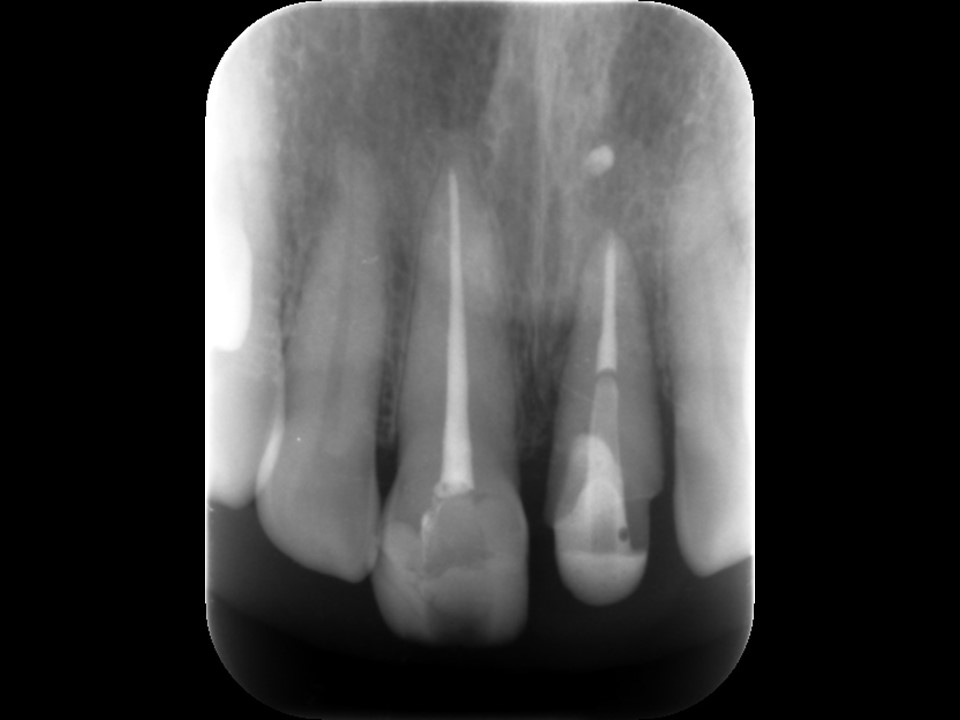

外科的挺出2か月後。歯槽骨の再生により、歯根周囲の黒いレントゲン透過像が消失している。歯の動揺も落ち着いた。

右側(向かって左)中切歯の根管治療後。外科的挺出を図った左側(向かって右)中切歯の歯根周囲に骨の再生を認める。歯根の吸収は認められない。